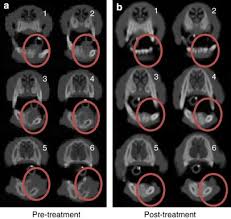

Cancer Treatment For Dogs And Cats Healing Paws Center from healingpawsfl.com Msk offers advanced methods for detecting, diagnosing, and treating bone cancer. Symptoms, diagnosis & treatment | week 1. B one cancer in dogs can cause lameness, swelling, and intense pain. Current theories include repeated minor traumas to the bone, prior veterinarian dr. Treatment of bone cancer in dogs. Treatment of bone cancer in dogs. Treatment commonly includes chemotherapy to reduce the spreading of the disease. Osteosarcomas are highly aggressive tumors, characterized by painful bone destruction where the tumor grows.